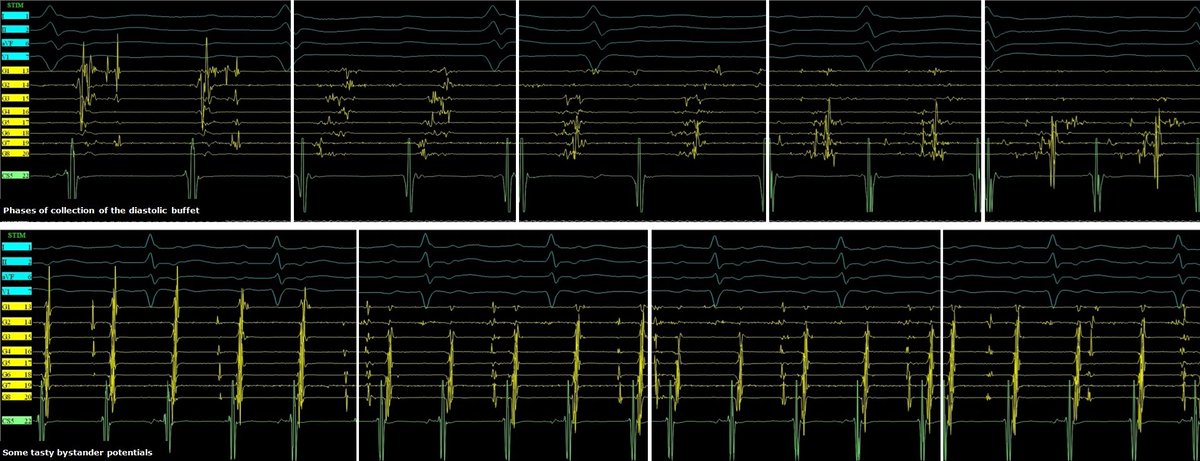

Celebrating 1yr since the publication of our Atlas of ConductSystemPacing #LBBAP #HBP! Thanks @ilpensiero for their support & to the readers for their trust! I hope it has been (& will be) useful to become confident in recognizing #CSP in your procedures! tinyurl.com/CSPAtlas